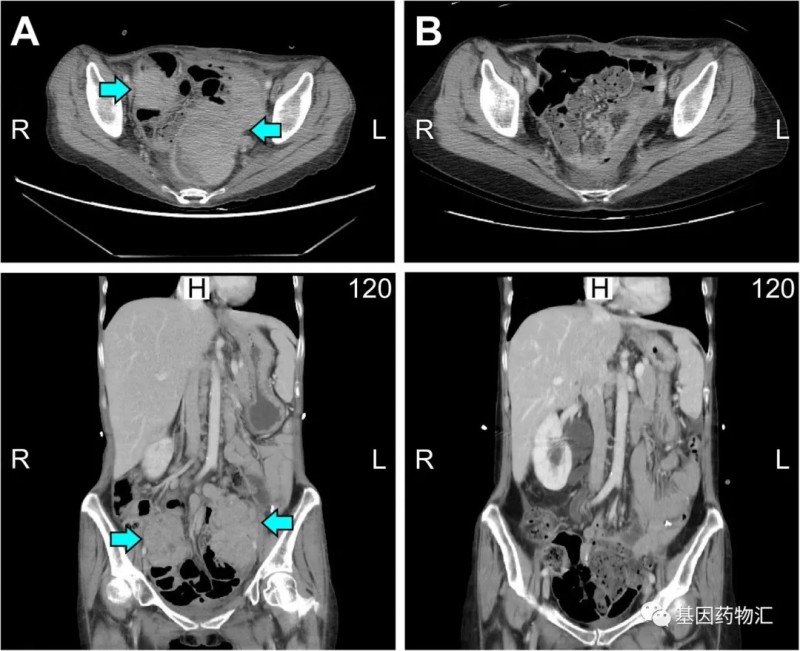

在影像学检查(CT检查)结果方面,治疗3个月后,患者的肿块开始明显消退,达到了临床部分缓解的标准;治疗9个周期之后,患者的病灶完全消失了!

左侧二图(A图)为2019年5月检查结果,右侧二图(B图)为2019年11月检测结果